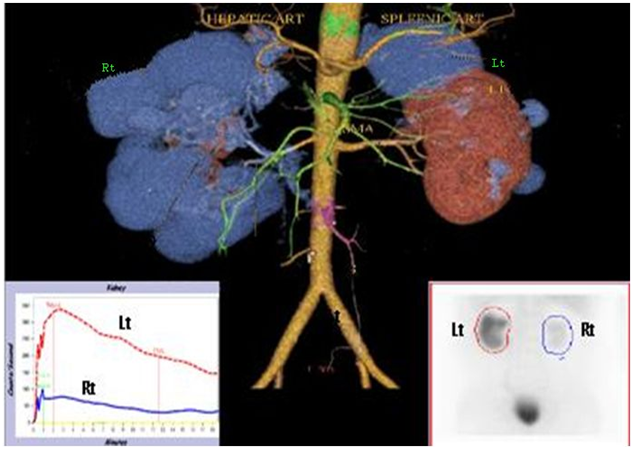

2-D ECHO showed good biventricular function, EF-62%, type 1 diastolic dysfunction, myxomatous AML suggestive of mitral valve prolapse(MVP) (Figure 4).

Figure 4 2-D ECHO showing myxomatous AML (arrow) suggestive of mitral valve prolapse(MVP).

ADPKD is associated with MVP in up to 25%.4 There are rare case reports of thrombosis in the inferior vena cava (IVC) due to enlarged cysts in autosomal dominant polycystic kidney disease.5 Our patient showed number of cysts to meet the required criteria for ADPKD6, with Stage II CKD, MVP, multiple colonic diverticulae and IVC thrombosis, had no positive family history, with only elder brother having late onset minimal change disease. Genetic workup for ADPKD is done. Literature review did not show association of IVC hypoplasia with cystic kidney disease.